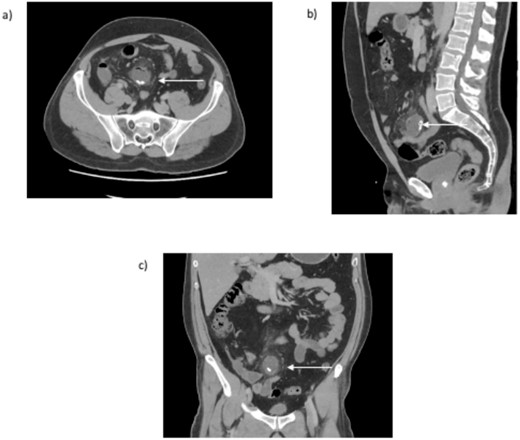

The computerized tomography of abdomen and pelvis (CTAP) with intravenous contrast scan (Fig. 1a–c) revealed a distended, fluid-filled blind-ending structure, containing calcified bodies, arising from the small bowel within the mid-lower abdomen with adjacent inflammatory changes. This reflected a likely case of Meckle’s diverticulitis. The appendix was normal, and the remaining abdominal viscera was unremarkable. No lymphadenopathy was evident, and the vascular structures were unremarkable. There was no abdominal fluid or gas.

CT abdomen and pelvis (a) transversal, (b) sagittal, and (c) coronal view. An arrow indicates the inflamed blind ending structure of the small bowel with calcified bodies.